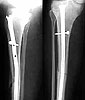

femur

humerus

tibia

The patient came to me two days after injury. Her general condition was not good with Hb 6.7 gm%. After Blood transfusions in the first stage I did standard femoral Interlocking - 10mm nail with two proximal screws. 3 days later I did Tibial and Humeral Interlocking nailing - 8mm and 6mm nail respectively with proximal locking only.

On discharge 10 days later she wass walking independently with Zimmer frame with full knee hip and shoulder movements. Xrays are attached.